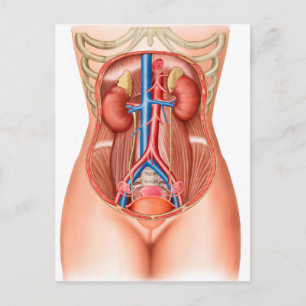

Anatomi i mänskliga organ vykort

Pris23,00 kr

Anatomi i mänskliga organ poster

Pris229,00 kr

Anatomi i mänskliga organ canvastryck

Pris1 425,00 kr

Anatomi i mänskliga organ hälsningskort

Försäljningspris 49,00 kr. Ursprungligt pris 54,00 kr.